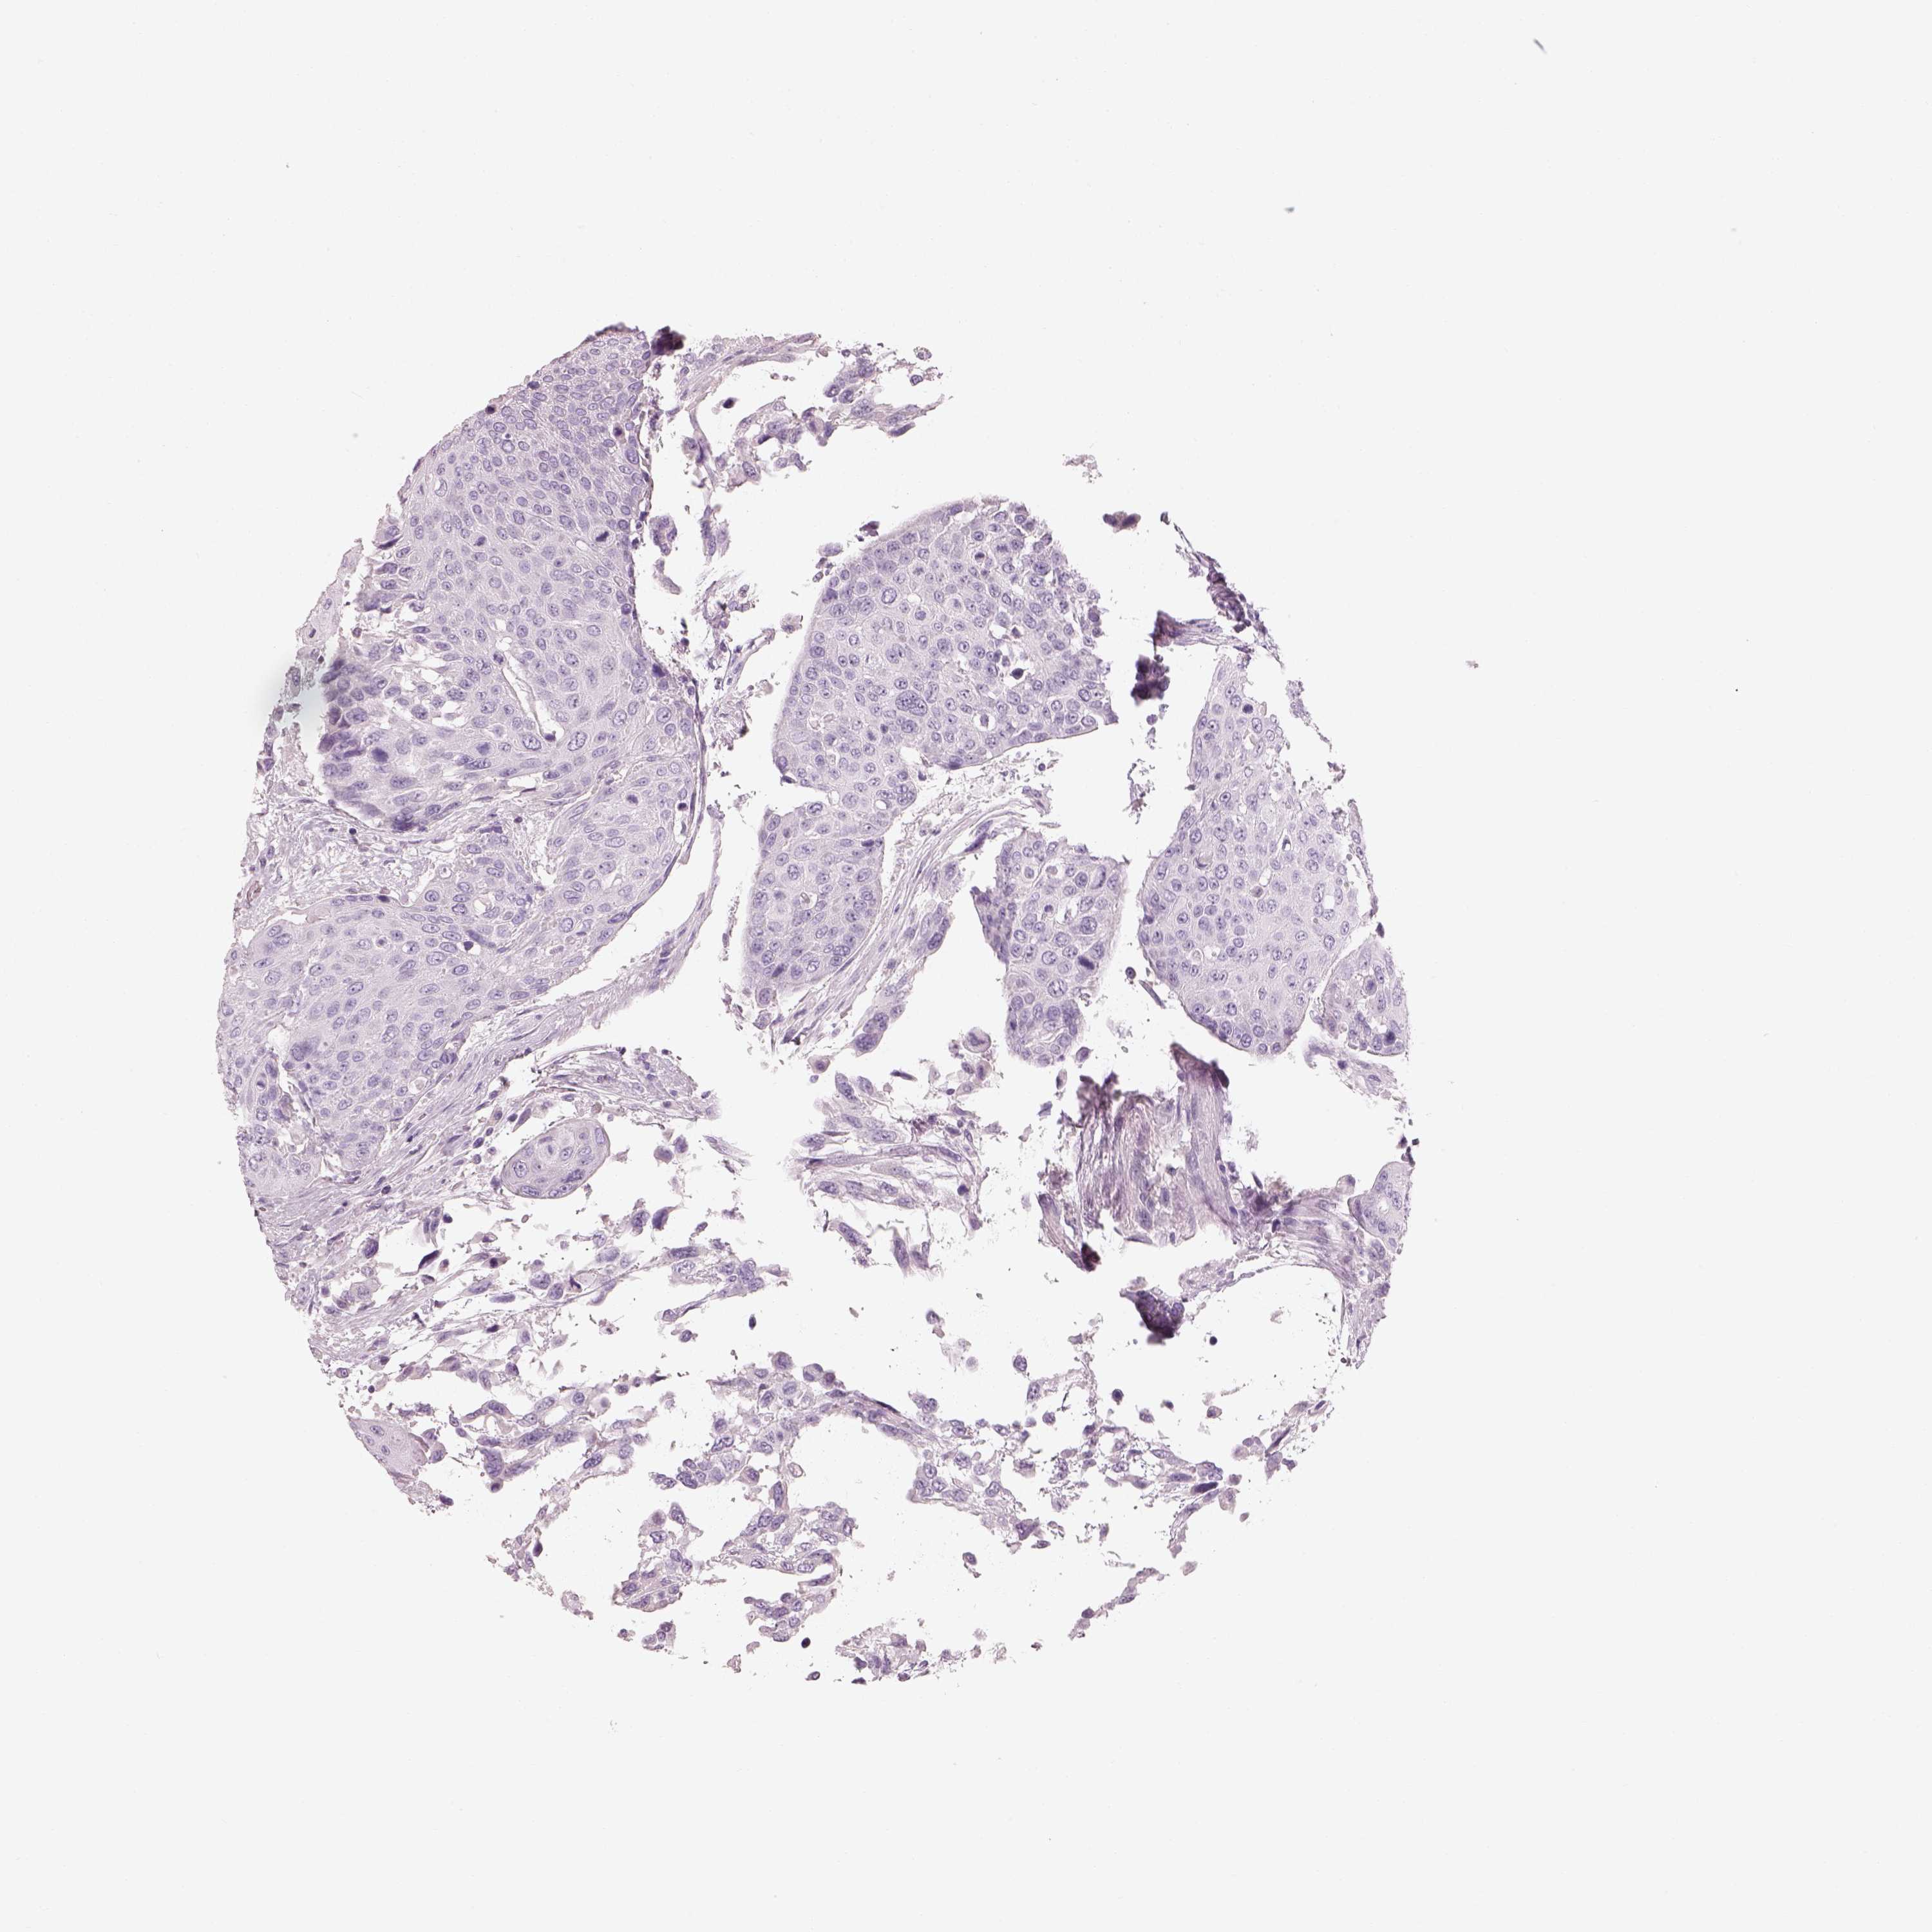

UROTHELIAL CANCER - Protein expressioni

A mouse-over function shows sample information and annotation data. Click on an image to view it in a full screen mode. Samples can be filtered based on level of antibody staining by selecting one or several of the following categories: high, medium, low and not detected. The assay and annotation is described here.

Note that samples used for immunohistochemistry by the Human Protein Atlas do not correspond to samples in the TCGA dataset.

Antibody stainingi

Antibody staining in the annotated cell types in the current human tissue is reported as not detected, low, medium, or high, based on conventional immunohistochemistry profiling in selected tissues. This score is based on the combination of the staining intensity and fraction of stained cells.

Each image is clickable and will lead to virtual microscopy that enables deeper exploration of all samples and also displays staining intensity scores, fraction scores and subcellular localization as well as patient and tissue information for each sample.

Antibody HPA043261

Antibody HPA043264

Antibody HPA044028

Urothelial carcinoma, High grade

Urothelial carcinoma, NOS

Urothelial carcinoma, Low grade